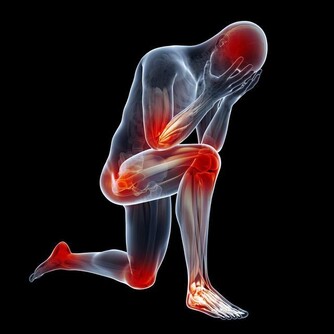

3、虛弱,因為身體無法正常供血,肌肉無法得到血液,會讓你覺得不管做什麼動作都很困難!